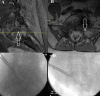

Results: Collectively, 19 cases described endoscopic spine surgery for spinal oncologic care. Endoscopic spine surgery has been employed for the care of patients with spinal tumors under the following 4 circumstances: (1) to obtain a reliable tissue diagnosis; (2) to serve as an adjunct during traditional open surgery; (3) to achieve targeted debulking; or (4) to perform definitive resection. These cases employing endoscopic techniques highlight the versatility of this approach and its utility when applied to the right patient and with an experienced surgeon.